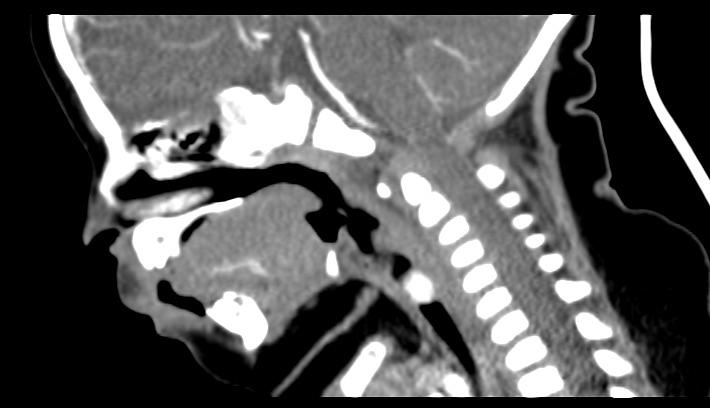

1.2诊断标准与方法对于可疑SGH患儿均需行纤维喉镜检查,声门下单侧或双侧局部隆起,表面光滑、暗红色,阻塞声门下气道,则高度怀疑SGH(图1)。颈部增强CT见声门下局部软组织增厚,气道变窄,增强扫描强化明显(图2a,b,c),诊断明确后给药。

颈部增强CT:左侧声门下局部软组织增厚,向气道内突起,强化明显。